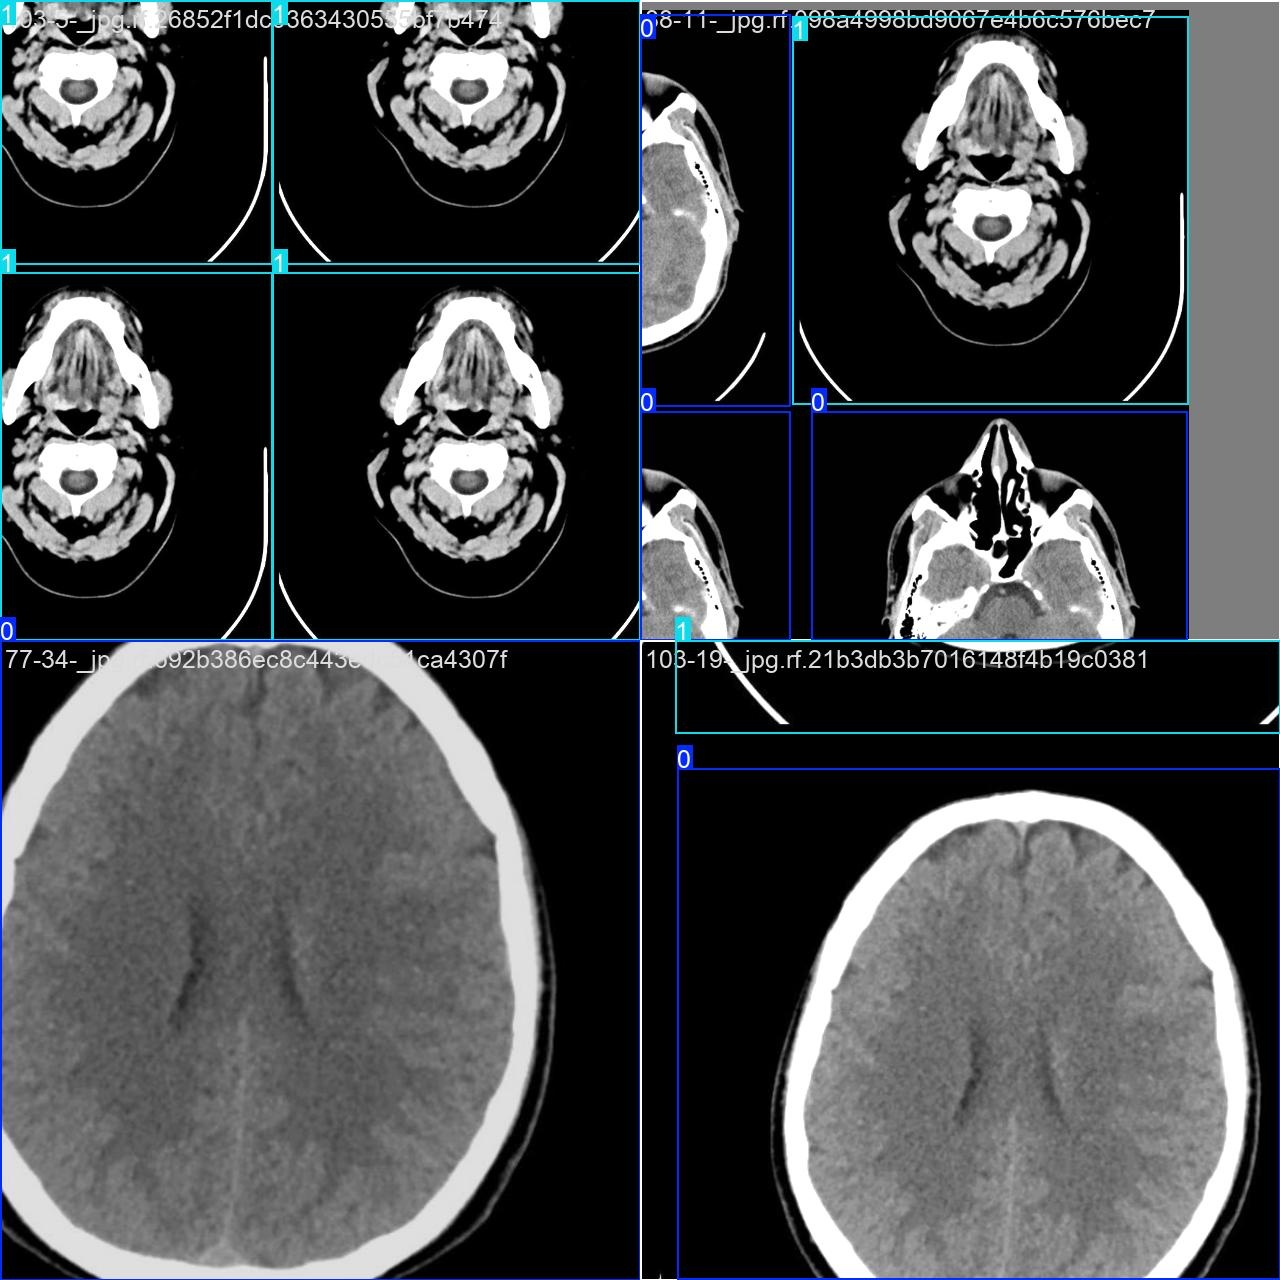

部分数据集图像如下图所示:

部分标注如下图所示: